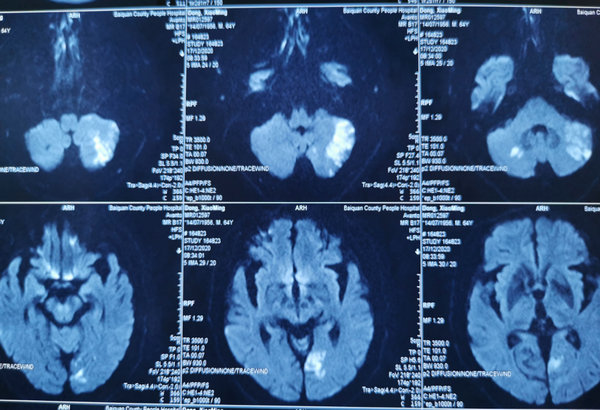

63岁的董先生,因阵发性耳鸣、左下肢无力10天,入住我院神经内科三病区救治。经颅脑MRI检查显示左侧颞枕叶、双侧小脑半球急性脑梗死,给予双联抗血小板聚集、强化他汀、改善循环等对症治疗基础上,又行全脑血管造影,发现患者的基底动脉近端狭窄严重,大于90%,近于闭塞。基底动脉至关重要,若不及时解除病变,随时可能再次出现脑干和(或)小脑梗死,导致呼吸循环功能衰竭,危及生命。由于基底动脉穿支众多,支架植入时挤压斑块可能导致穿支血管堵塞,在所有血管内支架手术中难度最高,风险最大。在与家属充分沟通后,同意实施基底动脉重度狭窄支架植入术。

颅脑MRI检查